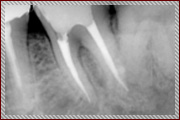

上記は歯のレントゲン写真です。二本足のように、歯が歯茎に埋まってますが、右の歯の黒い部分(二本足のつけ根の部分)が菌に冒されてます。 |

非常に細かい部分ですが、顕微鏡を使い、菌に犯されているところを治療した後にレントゲンを取りました。 |